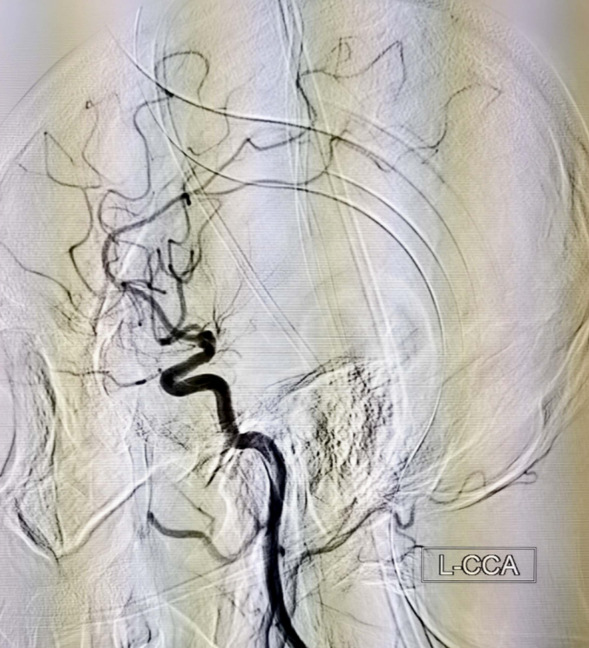

术前左侧颈内动脉侧位造影